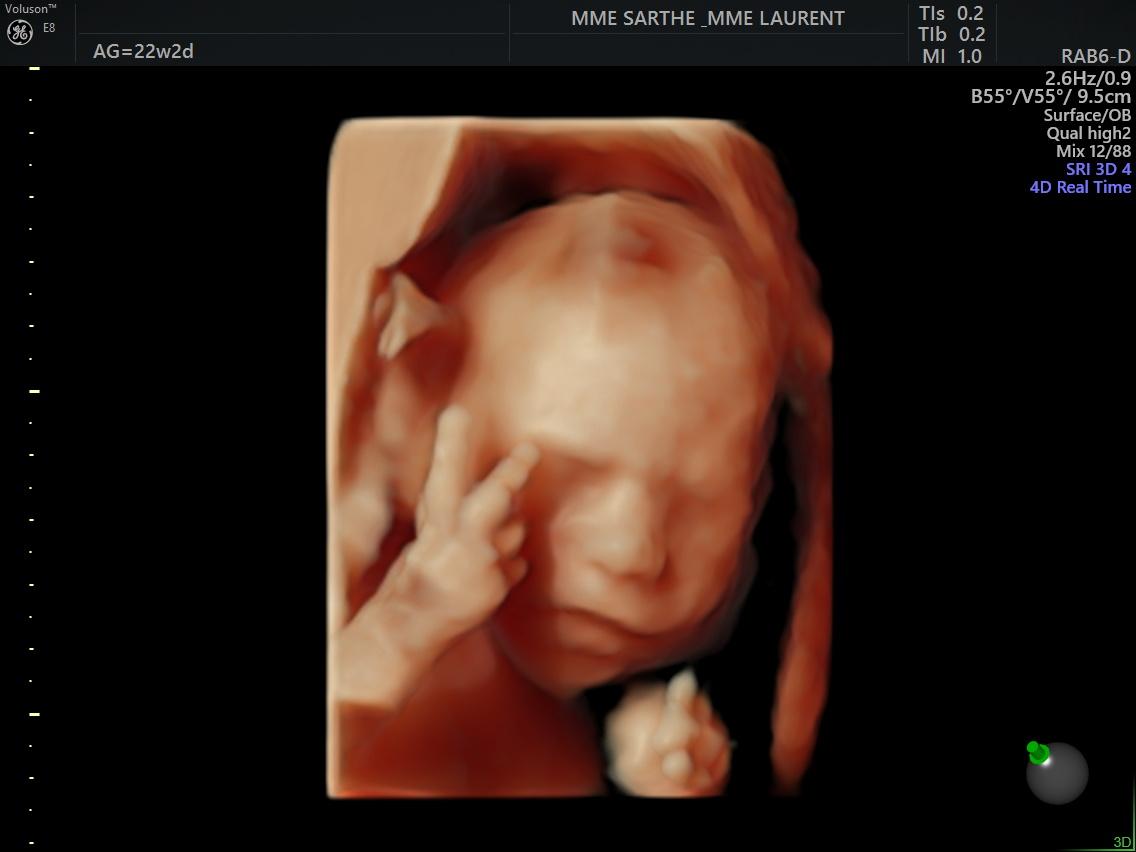

- l'échographie du 2 ème trimestre est réalisée entre 20 et 24 semaines d'aménorrhées (idéalement entre 21-23 semaines).Votre bébé a bien grandi et il est difficile de le visualiser en entier. C'est le moment idéal pour bien vérifier la vitalité de votre bébé à travers ses mouvements et le liquide amniotique , le bon développement de ses organes, sa croissance au travers des mesures de sa tête, de son périmètre abdominale et de son fémur qui permettront de donner une estimation de son poids ,et la localisation du placenta.

Si la position du bébé le permet, une visualisation en 3D vous permettra d’avoir une première image de son visage.